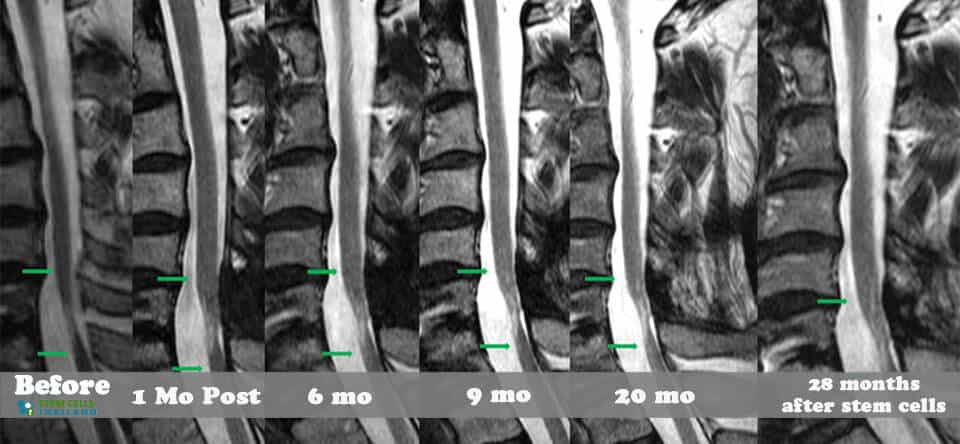

組織、軟骨或韌帶的新?lián)p傷對干細胞治療的反應要好得多。治療后的康復需要大量的奉獻和康復訓練。初次治療后約2-3個(gè)月,身體改善明顯,且效果是永久性的。[2]